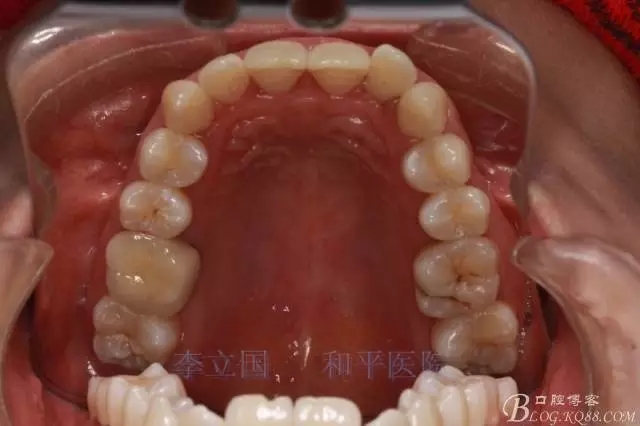

1.拔除14、24、31。

1.患者上前牙直立,面型前突,典型的嘴凸牙不吐,關(guān)鍵是前牙轉(zhuǎn)矩控制,建議使用高轉(zhuǎn)矩托槽。

3.上頜應(yīng)用支抗釘。表麻下在56牙槽間隔植入,注意因使用的為鈦合金釘,一直保持植入角度與骨面成60度角,不要垂直植入再改變角度。要求即刻加載,即刻加載力值2盎司。

4.使用長(zhǎng)牽引鉤,使?fàn)恳咏项M骨阻抗中心,防止上頜骨的順時(shí)針旋轉(zhuǎn)。

5.回收過程中,上下前牙輕搖椅,防止覆合加深。